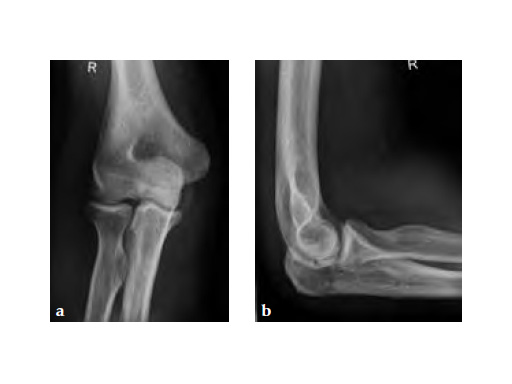

The LCP Hook 3.5 enables tension-band plating with use of 3.5mm screws. The Hook 3.5 was primarily intended for the treatment of simple fractures of the olecranon as well as osteotomies of the olecranon following distal humeral fracture. It has also shown benefits in avulsion fracture of the distal tibia and fibula.

Simple olecranon fractures and osteotomies as well as avulsion fractures of the medial and lateral malleolus treated with traditional tension-band fixation methods are often followed by complications. This is especially evident in patients with poor bone stock and complications include loss of reduction, migration of K-wires and hardware prominence. The LCP Hook 3.5 is a satisfactory alternative fixation.

Fig 1ab Preoperative AP and lateral x-rays.